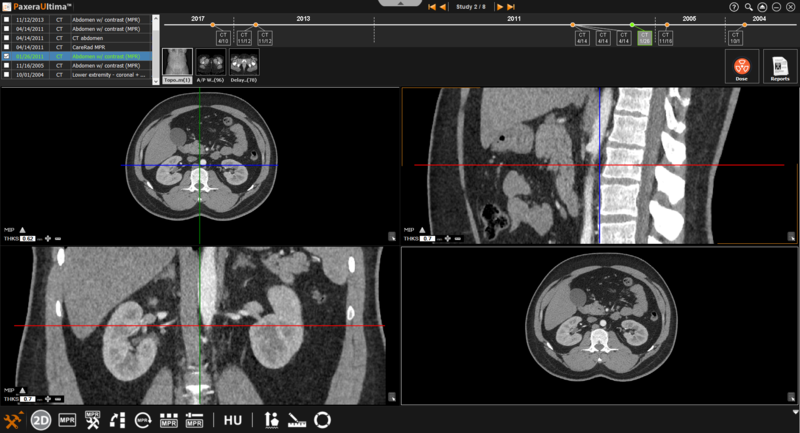

3. The study viewer will change into MPR/MIP mode, an overview of this mode and along with its tools are given below:

MPR Planes

The image windows will have colored lines that represent different planes as shown below: